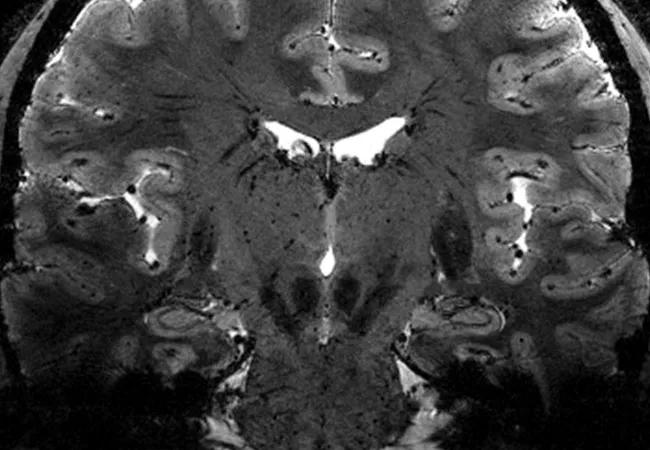

Several MRI modalities can be harnessed to better assess the severity and progression of multiple sclerosis (MS), but improved acquisition and post-processing methods are needed for reliable evaluation of cortical lesion load. So suggest new findings from Cleveland Clinic researchers published in Multiple Sclerosis Journal.

The myelin loss that is the hallmark of MS is particularly difficult to detect in the cerebral cortex, even with advanced MRI techniques. “We undertook this study to quantify how well these MRI techniques improve cortical lesion discovery,” Dr. Zheng explains.

The researchers examined how well three available advanced MRI modalities — MTR (magnetization transfer ratio), T1T2R (T1-weighted/T2-weighted ratio) and T2w (T2-weighted signal) — could determine areas of demyelination. They used these modalities to perform postmortem MRI studies on nine patients who had had primary or secondary progressive MS.

Following MRI acquisition, the researchers studied tissue samples from the cerebral cortices of each brain to determine how accurate the imaging techniques were in detecting cortical demyelination based on how much myelin proteolipid protein was present.

Of the three modalities, T2w was the most accurate in determining areas of demyelination (71% accuracy), followed by T1T2R (42%) and MTR (39%). T2w also had the highest specificity (46%) in detecting demyelination.

The effectiveness of T2w — particularly its role in determining T1T2R — can expand the effectiveness of MRI, Dr. Zheng notes. “We are excited about the possibility of T1T2R as a tool for mapping cortical myelin,” she says. “The fact that we can calculate the T1T2R map with routine T1w and T2w images makes T1T2R a possible new tool for myelin mapping.”

While all three MRI techniques were relatively accurate in detecting areas of demyelination, their specificity was somewhat limited. Dr. Zheng believes this may be because conventional MRI is more sensitive to cortical changes other than demyelination. “This is why we need to improve our ability to use MRI in managing MS,” she says. “Higher-resolution imaging and better processing will go a long way in identifying changes in the cortex in these patients.”